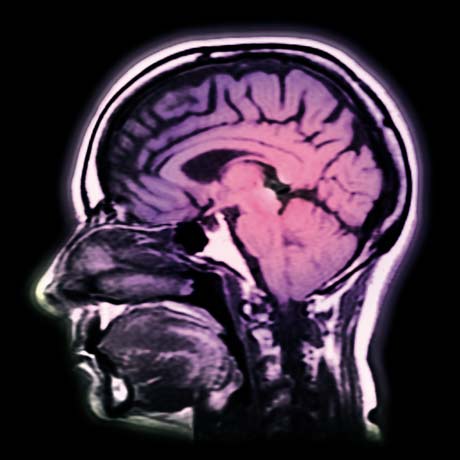

Bewusstsein und Sprache gehören eng zusammen: Neurologen suchen die Ursachen von Problemen mit Sprache und Wörtern.

Doch wer denkt, es handle sich bei den Silben- um Glasperlen-Spielereien eines Forschers im Elfenbeinturm, fehlt. Jacobs Forschungen haben einen hohen Anwendungsbezug und damit Nutzwert für Klinik und Schule. Wir sind inzwischen in der Lage einzelne Lesestörungen bei Kindern mit Hilfe von lexikalischen Entscheidungstests in Verbindung mit einem EEG und bildgebenden Verfahren nachzuweisen, sagt Jacobs, der von 1992 bis 1996 als Leiter der Gehirn und Sprachgruppe am Centre de Recherches en Neurosience Cognitive in Marseille gearbeitet hat. Bislang kennt die neuropsychologische Forschung neun verschiedene Typen von Lesestörungen, die von dem Problem, Worthälften zu unterscheiden (Neglect-Dyslexie) hin zum Problem, unbekannte Wörter (phonologische Dyslexie) zu verstehen, reicht.